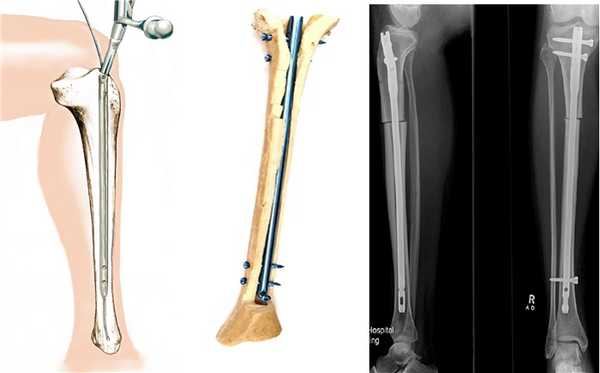

Остеосинтез стержнями (штифтами)

Эта методика получила наименьшее распространение по сравнению с двумя другими (пластинами и аппаратами). Несомненным достоинством является стабильная фиксация, что позволяет оперировать сразу обе конечности и обеспечивает раннюю функцию и опороспосбность. Суть методики заключается в том, что после предварительного рассверливания костномозгового канала бедренной или большеберцовой кости в него вставляется штифт соответствующего диаметра.

Схема введения, положение штифта внутри кости и рентгенограммы после операции

Несмотря на то, что штифты вводятся через небольшой разрез, нельзя считать эту методику малотравматичной. Существует риск развития серьезных осложнений. Если, допустим, при использовании аппарата Илизарова воспаление или нагноение носит локальный, поверхностный характер и легко излечивается, то при интрамедуллярном остеосинтезе нагноение грозит распространением процесса по всему костномозговому каналу. Также очень сложно добиться симметричной коррекции обеих ног, что имеет важное значение в косметической хирургии.

Учитывая риск развития серьезных осложнений, не хотелось бы рекомендовать эту методику при эстетической коррекции формы ног. Имеется целесообразность применения штифтов при удлинении, когда длительные сроки фиксации аппаратом Илизарова значительно снижают качество жизни пациентов.